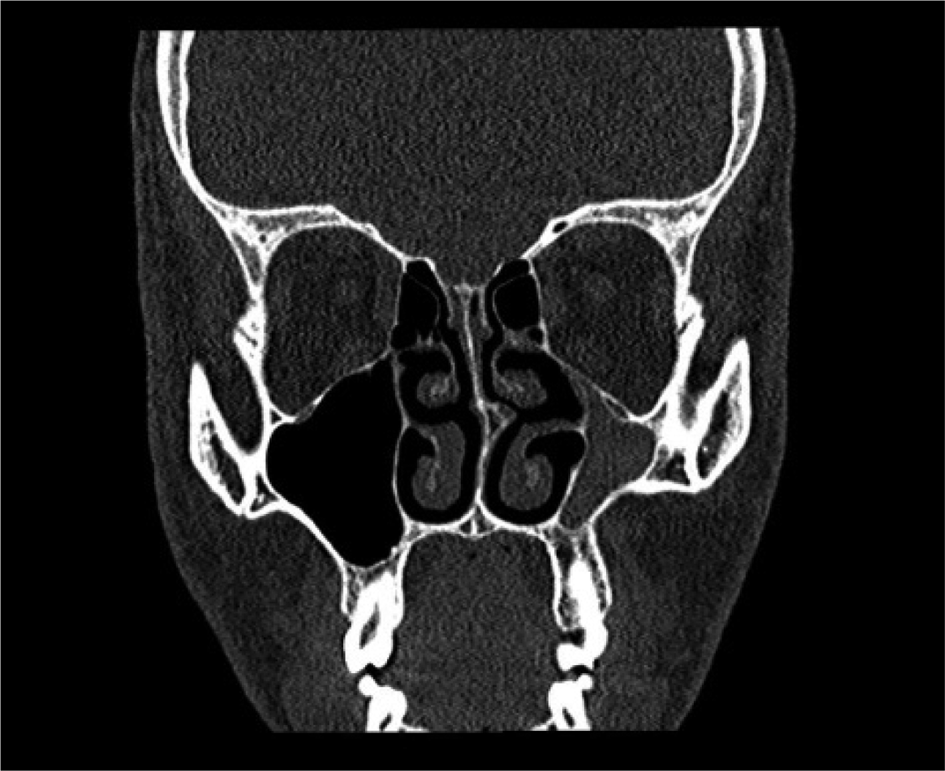

General symptoms of sinusitis were present in 21 patients and absent in 33 patients. Eleven patients had grade I (Figure 1), 35 patients had grade II (Figure 2) and 8 patients had grade III (Figure 3) chronic maxillary atelectasis. Seven patients met the silent sinus syndrome criteria; one patient with chronic maxillary atelectasis grade III was symptomatic and therefore not considered to have silent sinus syndrome. Table 2 reports the clinical features.

Fig. 2. Coronal computed tomography scan of the paranasal sinus demonstrating inward bowing of the sinus walls and opacification of the sinus (left) (grade II chronic maxillary atelectasis).